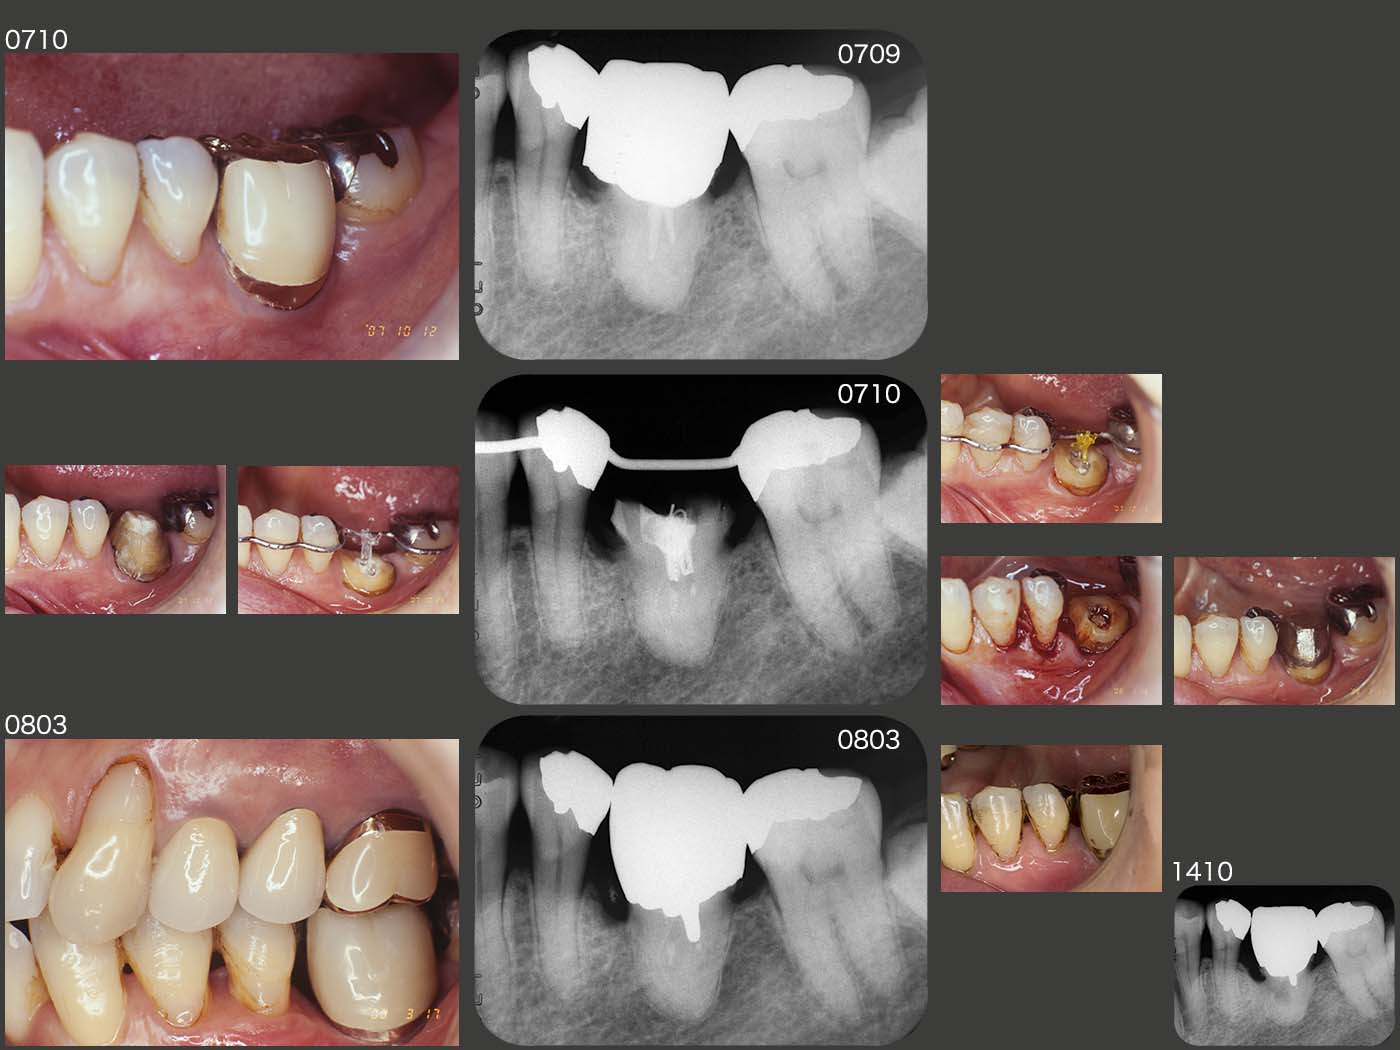

2007年10月のリコール時,移植された左下6の近心に7mmの歯周ポケットが認められた.ここで,歯周ポケットの改善および頰側の歯頸線を隣在歯に沿わす目的で,冠を外し,矯正的挻出を試みた.しかし,1ヵ月少々矯正力を加えたにもかかわらず,移植歯はまったく動かなかった.仕方なく歯周外科を行い,08年3月に再度硬質レジン前装冠を装着した.同月のデンタルX線写真から,歯根の下方には歯槽硬線が観察されるが,上部は観察されず,歯槽骨との癒着が生じているものと推測された.

スライド右下に14年10月の状態を示すが,左下5とのコンタクトに離開が生じ,デンタルX線写真から歯根にも置換性吸収を思わせる像が認められるようになった.